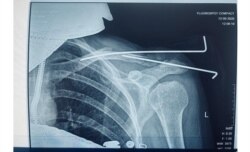

Пасьля вызваленьня Кірыл зьвярнуўся ў лякарню, дзе яму дыягнаставалі пералом правай ступні, пашкоджаньні левага пляча і перадплечча, правага сьцягна. Некаторы час ён прабыў у гіпсе.

Калі Кірылу зламалі нагу, ён дакладна ня ведае. Ён кажа, што ня памятае, у які менавіта момант у яго пачала балець нага, але гэта было з самага пачатку. Ці то яму на яе наступілі, ці то гэта адбылося ў «калідоры». Але за чатыры дні ён зьмірыўся з тым, што ў яго баліць нага.

Як высьветлілася, куля пацэліла мне ў плячо, разьбіўшы ключыцу на аскепкі. Уласьцівасьць гумавых куль — пранікаюць неглыбока, але ствараюць магутную ўдарную хвалю. Таму страляць гумавымі кулямі ў корпус і ў галаву ні ў якім разе нельга.

У мяне атрымалася кантузія на палову тулава (варта было крыху напружыць цягліцы — і адразу быў боль да самага чэрапа), гематома на сьпіне, якая і празь месяц да канца не сышла, і адкрыты пералом з ранай больш за 10 см у даўжыню і некалькі сантымэтраў у шырыню. Мне ў плячо кожны дзень закладвалі па два тампоны, каб хоць неяк спыняць кроў.

І зноў: некалькі дзён ляжаць у лужыне ўласнай крыві — гэта цяпер шанцунак. Калі на першай апэрацыі мяне ўводзілі ў наркоз, дактары абмяркоўвалі, ці варта захоўваць нагу 16-гадоваму хлопцу ў штучнай коме, або ён мае больш шанцаў выжыць з ампутацыяй. У часе другой апэрацыі, ужо пад мясцовай анэстэзіяй, я тры гадзіны слухала, як дактары пілуюць маю ключыцу. Як у іх не атрымліваецца і робяць наноў. Як пальцамі перабіраюць цягліцы і ўстаўляюць жалезныя сьпіцы ў абломкі косткі. Як крэсла пада мной развальваецца ад старасьці, а лямпа падае на галаву. У другім канцы апэрацыйнай хірург гучна абураўся: «Вось прыдуркі, яйцы ім паадрываць. Яны па мітынгах ходзяць, а я ім чацьвёрты дзень кулі з азадкаў дастаю!»

Дактары не казалі, што ў мяне пералом, да наступнага дня. Празь дзень сказалі, што адкрыты пералом. Яшчэ празь дзень, што будуць мне зьбіраць ключыцу. Як мне сказалі, паводле ваенна-палявой хірургіі маё раненьне ацэньваецца як ня вельмі складанае. Нягледзячы на тое, што было тры апэрацыі на плячы і ўскладненьне на лёгкае.

Другі месяц я на бальнічным. Днямі мне выцягваюць сьпіцы… Два аскепкі косткі зрасьліся даволі роўна, адзін крыху выпірае — я ўжо цяпер магу адчуць невялікую выпукліну. Вядома, усё гэта баліць і цягне кожны дзень, але не кругласутачна і па-рознаму.

Часам, калі пераварочваюся, чую, як шчоўкае нешта. Гэта трохі жудасна. Але да гэтага прывыкаеш. Левая рука нашмат танчэйшая за правую — цягліцы атрафаваліся. І ёсьць цягучы боль уздоўж цягліц. Я думаю, гэта ўсё вернецца, калі здымуць павязку і я буду распрацоўваць руку. Дактары кажуць, колькі была зьнерухомленая рука, прыкладна столькі ж функцыі будуць аднаўляцца. Зрэшты, я цяпер адной рукой толькі коўдру ў чахол не запраўлю, а так усё магу. І працую адной рукой — не хачу падстаўляць калег.